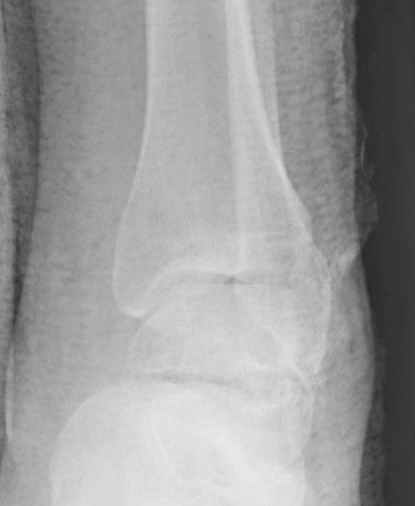

Вдогонку по поводу перелома таранной кости, больная 81, не страдает диабетом, перелом закрытый, в первый же день поступления ограничились временным наружным фиксатором (как на снимке).

Планировалась открытая фиксация после спадения отека, но больная пожелала лечиться по месту жительству в другом штате..

Примеры на снимке...